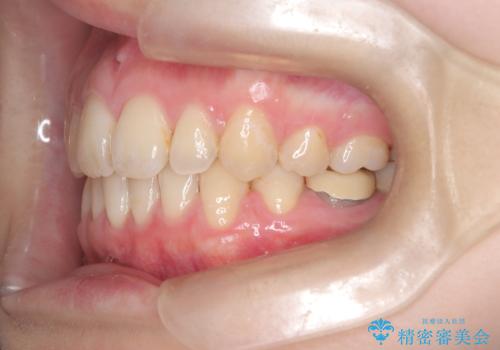

- 「歯のデコボコ、八重歯、口ボコが気になる」を主訴に来院された患者様です。

上下左右4番(4本)の歯を抜歯しワイヤー矯正で治療を行いました。

計4本の抜歯を行い、歯のデコボコと口元がすっきりし、大変ご満足していただけました。